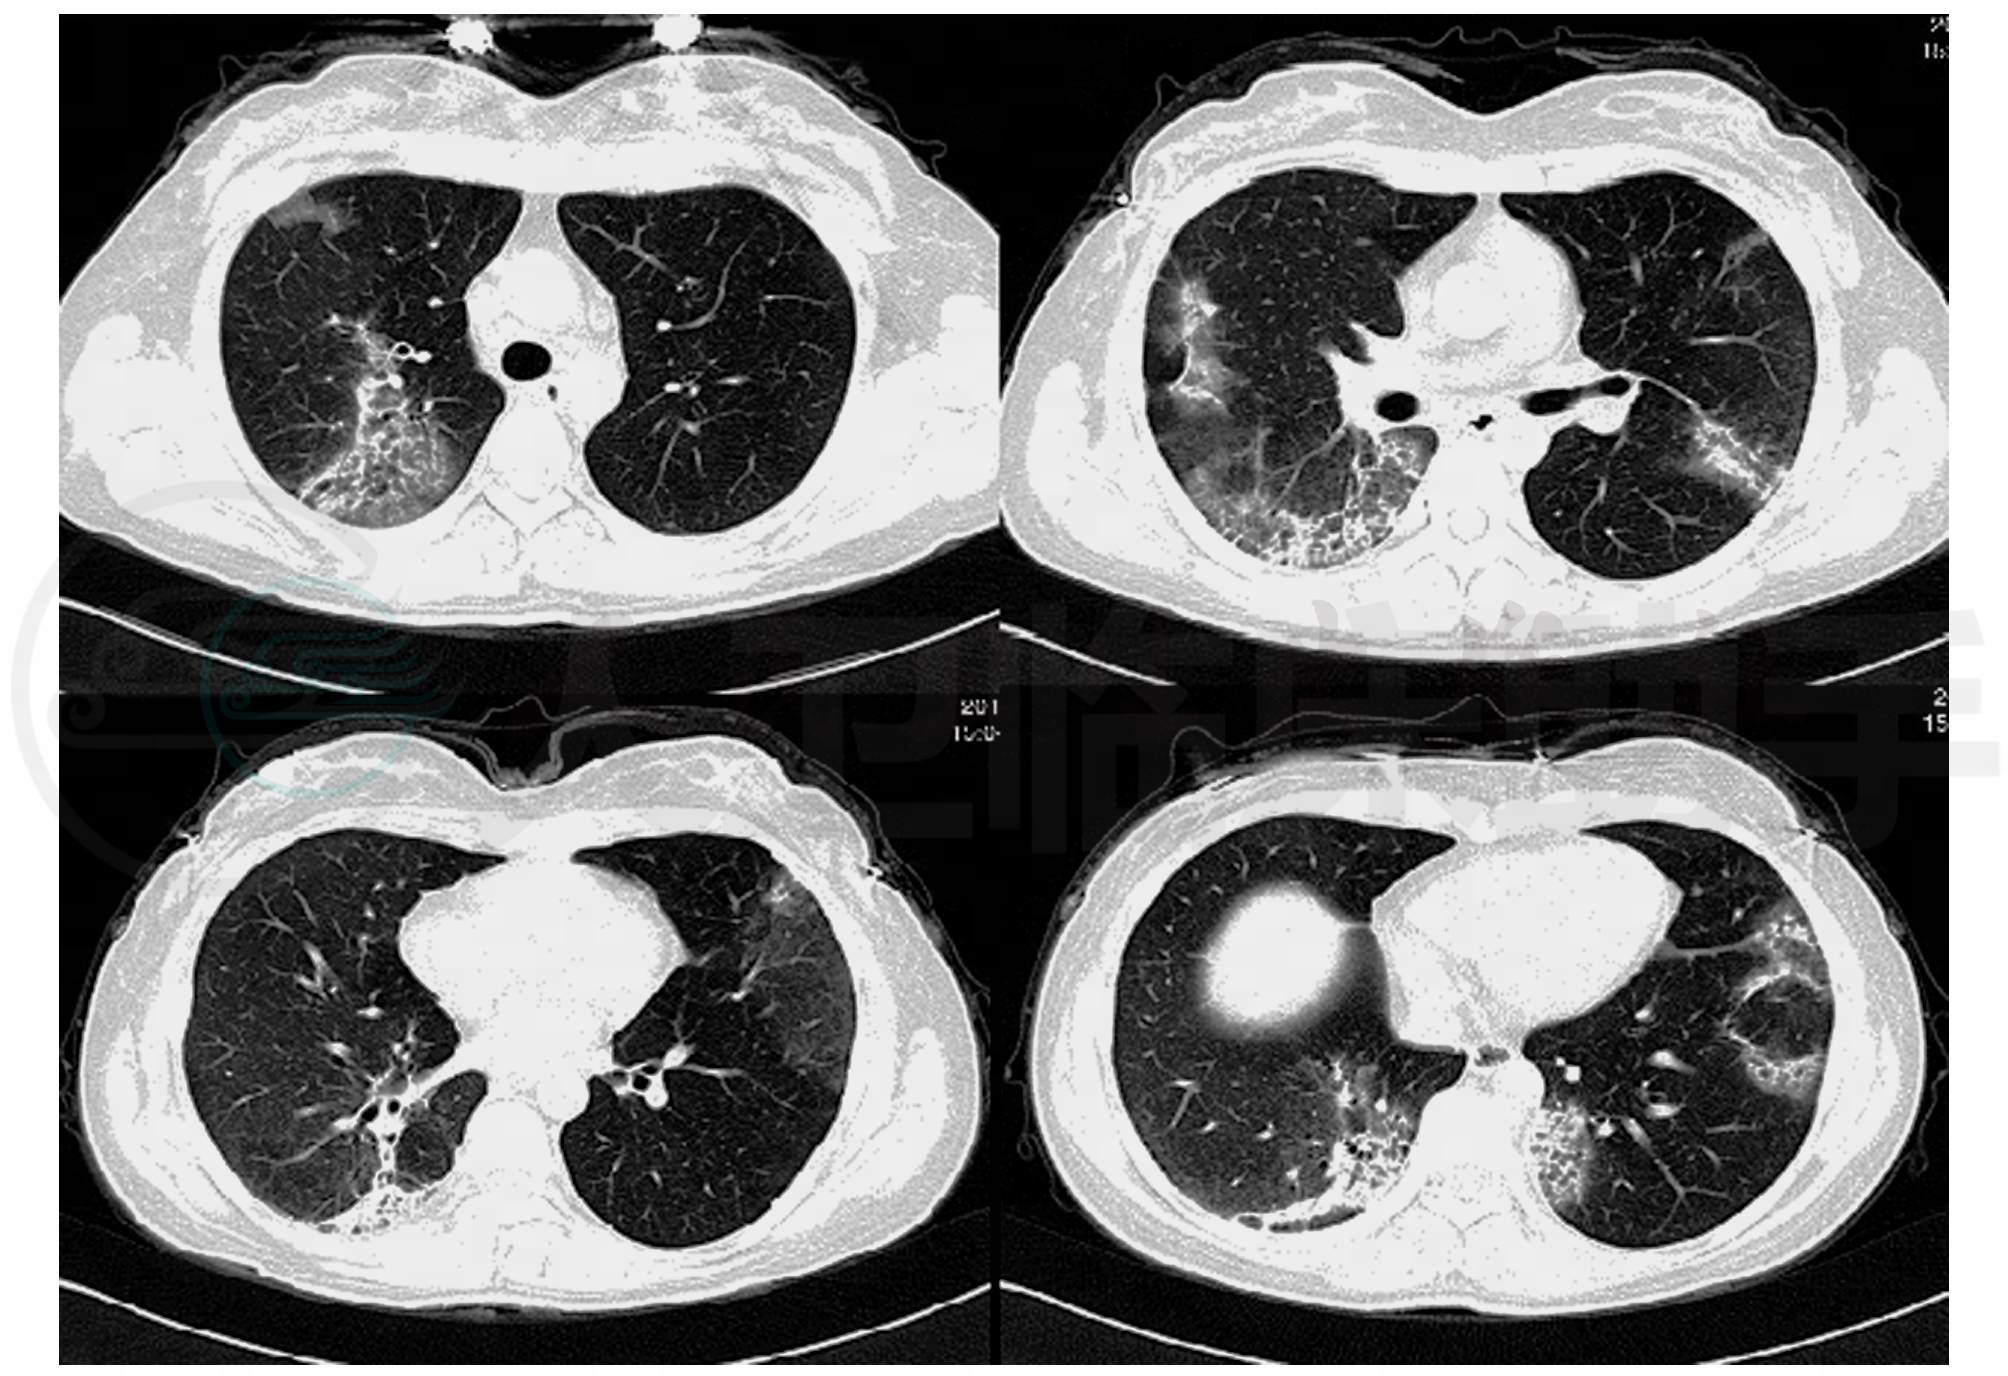

辅助检查:血常规:WBC:9.8×109/L,NEU%:70%,HGB:103g/L,PLT:396×109/L。肝肾功能:正常。血清离子:Na+:138mmol/L,K+:4.08mmol/L,Cl-:99.0mmol/L。DIC指标:PT:13.6s,DD:1.07μg/L,FIB:8.88g/L。CRP:93.4mg/L。血沉:67mm/h。血清补体:C3 1.93g/L,C4 0.35g/L。肿瘤标记物:NSE:4.95ng/ml,AFP:12.82ng/ml,CEA:2.05ng/ml,CA199:1.33U/ml,CA125:2.79U/ml。军团菌抗体:阴性。肺炎支原体抗体:1∶160,肺炎衣原体抗体:阴性,结核抗体:阴性。IgE:231.0IU/ml,IgG:11.4g/L,IgA:2.18g/L,IgM:1.27g/L。肺CT显示:双肺多叶段多发不规则致密影,其内见小叶间隔增厚,部分病灶内见支气管充气征,各层面未见肿大淋巴结(图1)。

图1 双肺多叶段多发不规则致密影,其内见小叶间隔增厚,部分病灶内见支气管充气征